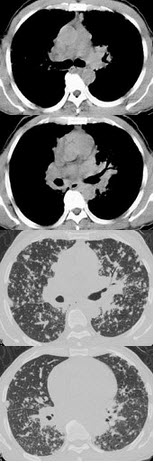

女,52岁,曾患有鼻窦炎,最近发现咳嗽发热,影像学检查如图,最可能的诊断为()

A.多发性肺脓肿

B.浸润型肺结核并空洞形成

C.韦格肉芽肿

D.结节病

E.肺转移瘤